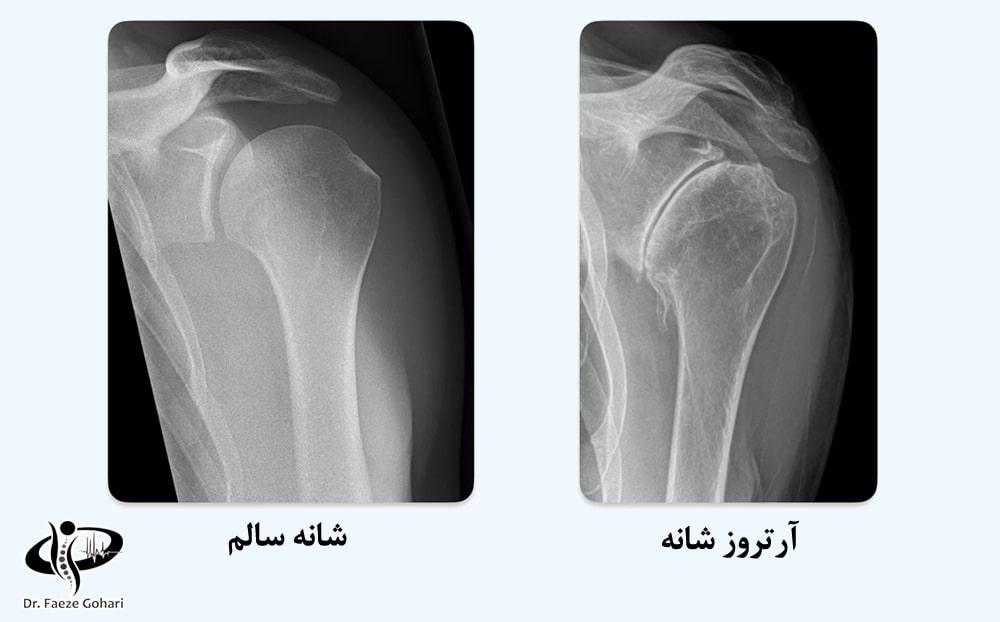

شانه، یکی از پیچیده‌ترین و قوی‌ترین مفاصل بدن، در صورت ابتلا به آرتروز و تحلیل غضروف، می‌تواند دچار درد شدید و محدودیت حرکتی شود. اگرچه بسیاری تصور می‌کنند تنها گزینه‌های درمانی جراحی یا تزریق استروئید هستند، اما روش‌های نوین و بازسازی‌کننده مانند تزریق سلول‌های بنیادی و PRP به‌عنوان جایگزینی کم تهاجمی و ایمن برای جراحی‌های پرریسک، مطرح شده‌اند.